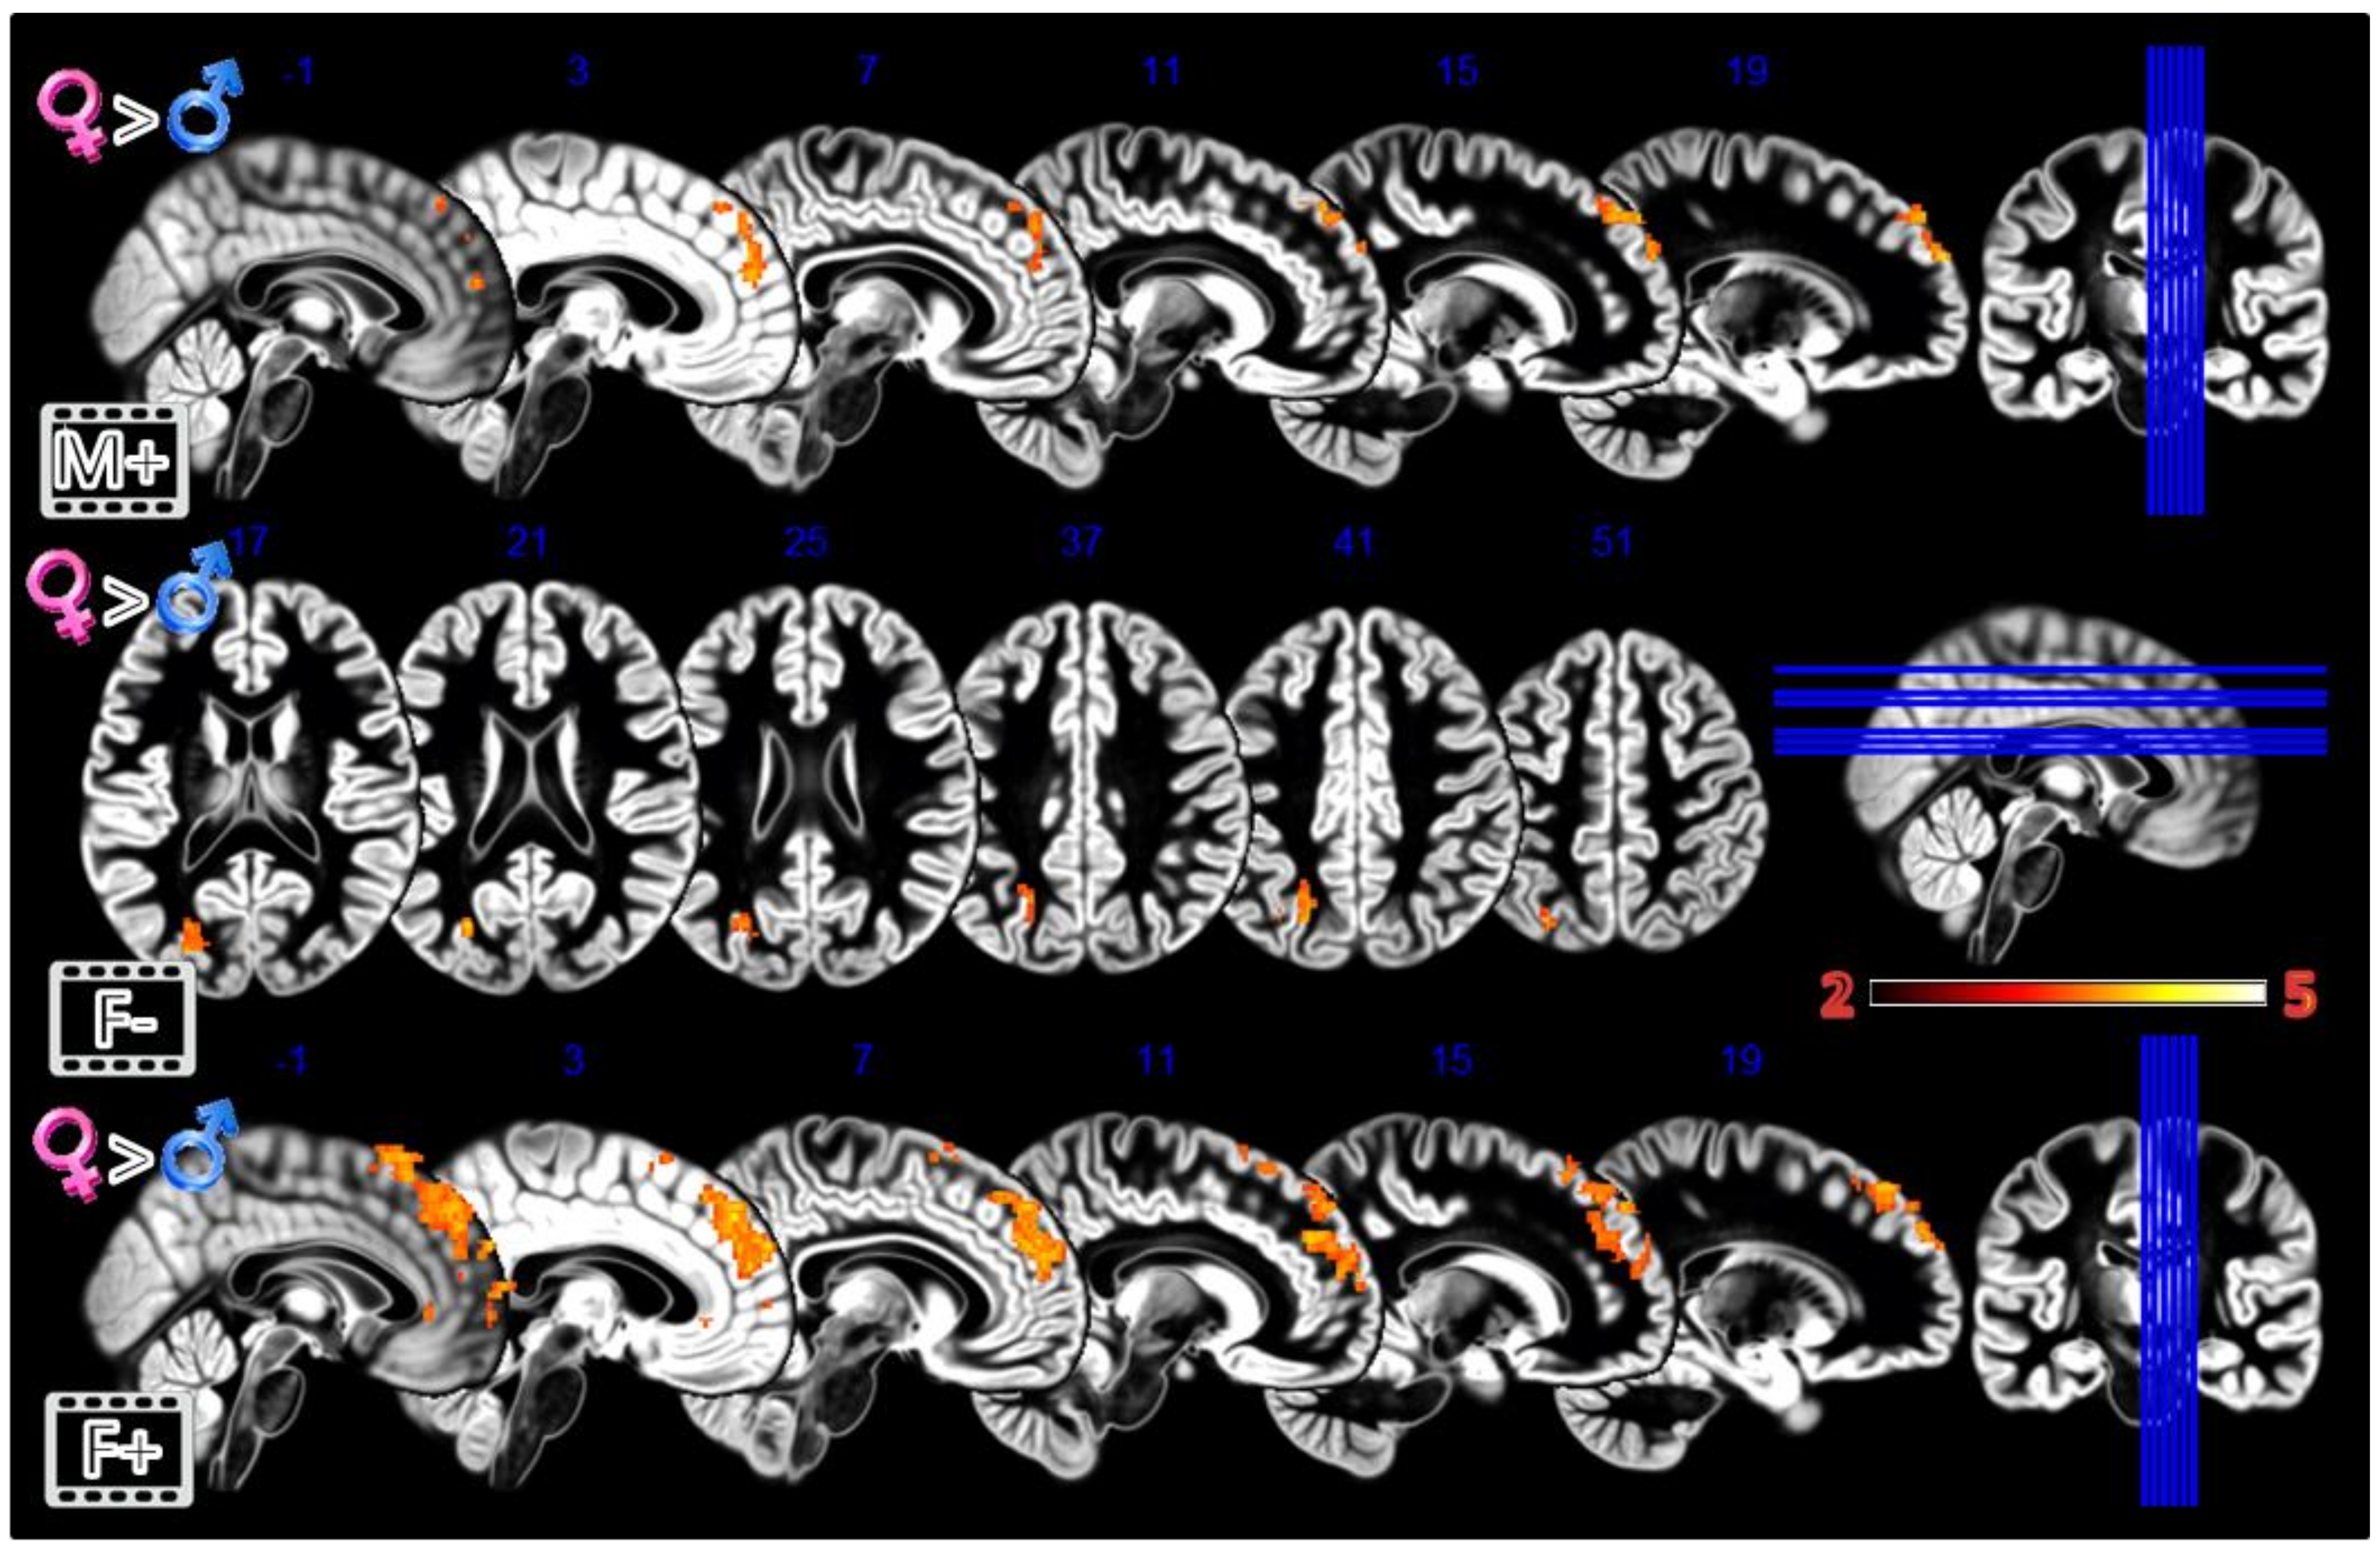

In the second experiment, Static Morphing (Figure 4, Table 1), the male group activated more the supplementary motor area (SMA) when looking at their own face; the female group activated more the dorsomedial prefrontal cortex (dmPFC).

Figure 4.

Group differences for the Static Morphing experiment. First row Males greater than Females for looking at own face, second row Females greater than Males for looking at feminized faces. In red significant clusters (p corr < 0.05) on a gray matter ICBM brain template, neurological convention, color scale in the bar maps for Z scores. In blue MNI coordinates in mm, and lines to show the slice positions on the orthogonal projections (right side of the figure).

In the third experiment, Dynamic Morphing (Figure 5, Table 1), the female group activated more the dmPFC when observing both observing the feminization or the masculinization of their face, but with a more widespread activation (2804 vs. 448 voxels) for congruent sex condition. Also, the defeminization produced more activations in females compared to males, but in the left superior parietal lobule and middle occipital gyrus.

Figure 5.

Group differences for the Dynamic Morphing experiment. All the rows Females greater than Males for masculinization (first row), defeminization (second row) and feminization (third row) morphings. In red significant clusters (p corr < 0.05) on a gray matter ICBM brain template, neurological convention, color scale in the bar maps for Z scores. In blue MNI coordinates in mm, and lines to show the slice positions on the orthogonal projections (right side of the figure).